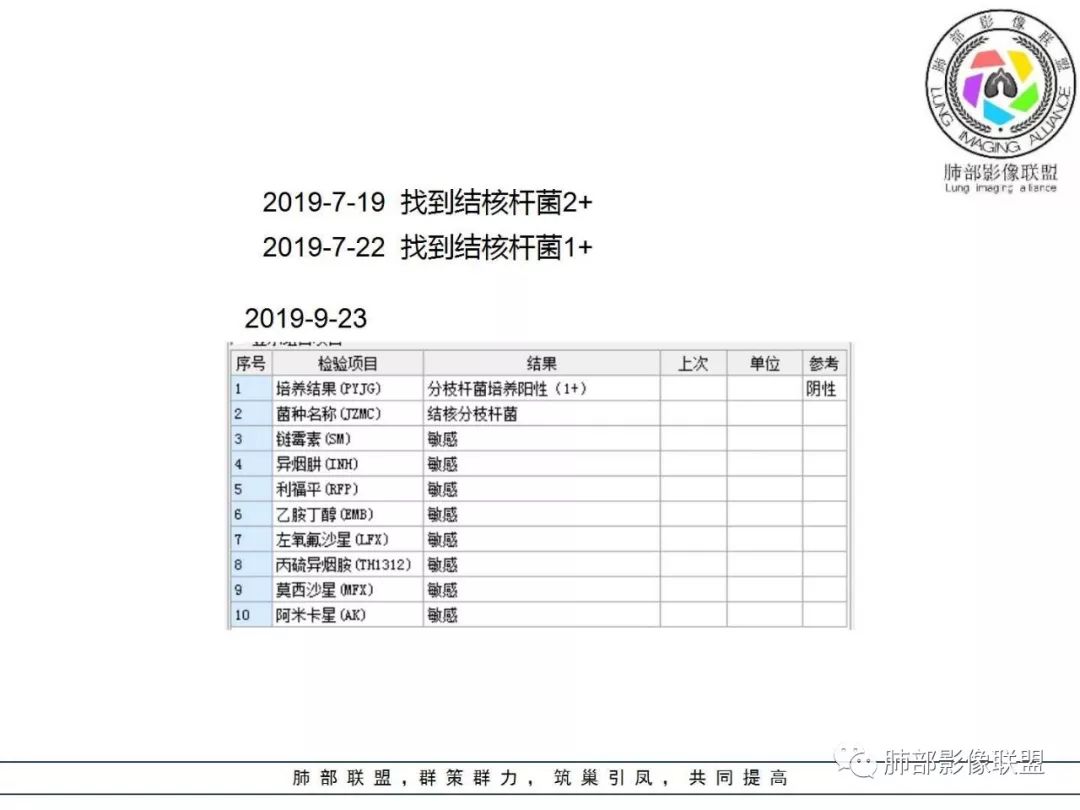

答案揭晓

04

间质性肺结核

1. 老年男性,发热为主诉,体温38°-39°,发热以午后及晚上为主,伴黄痰,CRP增高,临床病史支持感染性病变;

2. 肺气肿背景(小叶中心性肺气肿);双肺多发病灶整体沿血管支气管束及胸膜下分布,以上叶及下叶背段分布为主,有实变及GGO,边界清楚,有树芽,小叶间隔及中央间质增厚,叶间裂见到多发结节,部分支气管不规则牵拉扩张,提示病灶纤维化明显,结合临床病史,考虑病灶为间质性感染,肺门及纵隔内有钙化淋巴结,小叶间隔结节,考虑淋巴道增值性疾病可能,综合常规要怀疑间质性肺结核。

3. 该病例临床提示感染,有支气管扩张,提示纤维化,需要与感染后的OP鉴别,但是OP病灶常无结节感;间质性肺结核有时与不典型结节病鉴别也比较困难,结节病常以双肺门淋巴结增大为特征。临床上结核发病率较高。